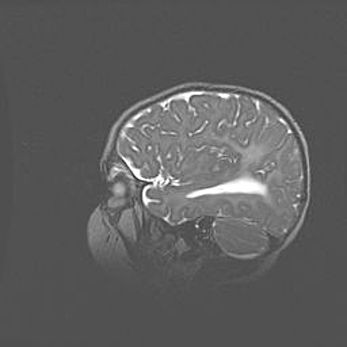

Мальформация Денди-Уокера. Киста задней черепной ямки.

Агенезия мозолистого тела.

Возраст: 2,5 месяца

Вес: 2420 г

Пол: женский

Окружность головы: 37 см

Срок гестации: 32 недели

Мальформация Денди—Уокера — редкий вид патологии ЦНС, представляющий собой врожденный порок развития каудального отдела ствола и червя мозжечка, ведущий к неполному раскрытию срединной (Мажанди) и латеральных (Лушка) апертур IV желудочка мозга. Для этогно синдрома характерна триада симптомов: гипотрофия червя мозжечка и/или полушарий мозжечка, кисты задней черепной ямки, гидроцефалия различной степени. В 70% случаев порок сочетается и с другими аномалиями головного мозга, в частности с агенезией мозолистого тела.